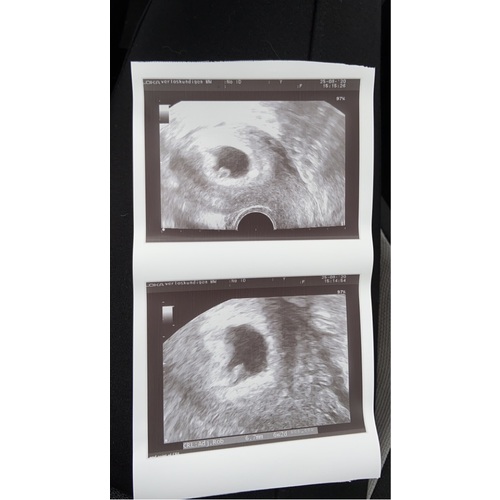

Geen ervaring mee, ik had zelf een uitwendige echo maar ik zie toch échtwel een mooi vruchtzakje met inhoud. Komt goed meid, ik duim voor je ♥️♥️

Wij ook precies hetzelfde verhaal. Met volle blaas en zowel inwendig als uitwendig nauwelijks wat te zien. Volgens mijn laatste menstruatie zat ik op 7+5. Maar eigen berekening ben ik nog niet zover. Later zag ze wat flikkeren en dat kon het hartje zijn. Nu gaan we donderdag as weer kijken, dan ben ik 8+3. Een week vol spanning. Hopelijk Dan wat meer te zien